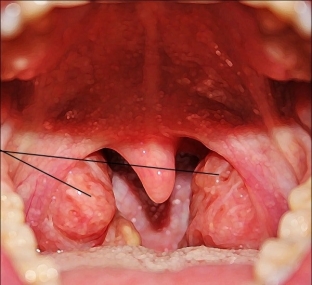

Adenoids – These are pathologically enlarged tonsils in the nasopharynx. The nasopharyngeal tonsil is part of the Walder-Pirogov lymphoid pharyngeal ring. The nasopharyngeal tonsil is well developed in children, and with age it decreases or even atrophies. The reasons for the formation of adenoids include a genetic predisposition to lymphatic-hypoplastic anomalies of the constitution.

There are 3 degrees of palatine tonsil enlargement depending on the symptoms of adenoids:

- 1 degree - adenoids cover the third part of the vomer and choanae. During the day, the child breathes freely, at night, in a horizontal position, nasal breathing is difficult.

- 2 degree – adenoids overlap half of the choanae and vomer in a child. At the same time, the child always breathes through his mouth and often snores in his sleep.

- 3 degree – adenoids completely or almost completely cover the choanae and vomer. Symptoms of adenoids of the 2nd degree are more pronounced.